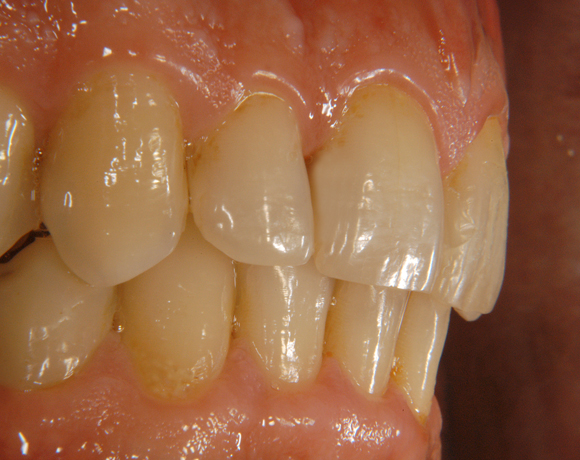

Bildlegende:

Bild 13 – 15: Fertige Füllungen